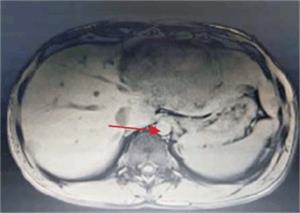

Tumoración que sustituye el lóbulo izquierdo con realce heterogéneo en la fase arterial que infiltra la vena suprahepática izquierda, contacta con la vena suprahepática media y la vena porta (figura 2) y (figura 3). Lesiones en los segmentos V y VIII. Extensas adenopatías en el hilio hepático. Nódulo peritoneal en fondo de saco de Douglas. Nódulo pulmonar derecho (figura 4).

Figura 2: Tumor a nivel de lóbulo izquierdo con hipervascularización central. Realce de la vena porta.